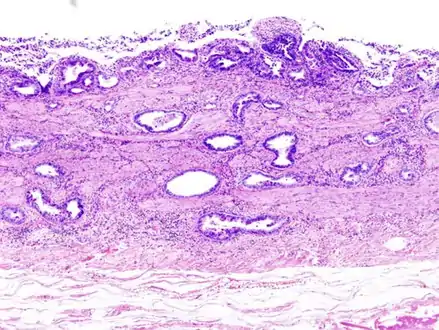

Gallbladder adenocarcinoma histopathology